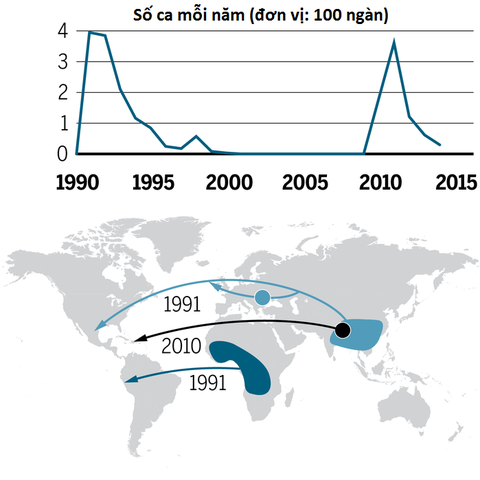

Quá trình vi khuẩn tả đến châu Mỹ trong 2 đợt dịch lớn gần đây - Ảnh: Science

Thomson nhận thấy châu Mỹ có 2 dịch tả lớn trong nửa thế kỷ qua: một bùng phát ở Peru sau lan rộng ra các quốc gia Mỹ Latin những năm 1991-1993 và một đợt khác ở Haiti năm 2010.

Các nhà khoa học đưa ra bằng chứng cho thấy dịch tả ở Haiti do lính gìn giữ hòa bình Liên Hiệp Quốc từ Nepal vô tình đưa vi khuẩn vào quốc gia này. Trong khi đó, đợt tả bùng phát đầu thập niên 90 đi bằng 2 đường: một qua châu Phi đến thẳng Peru, một từ Nam Á đến Mexico và có thể "quá cảnh" ở Đông Âu. Tất cả đều xuất phát từ châu Á.

Ở châu Phi, các nhà khoa học chỉ ra 11 vi khuẩn tả đặc biệt có nguồn gốc châu Á đã gây ra những dịch bệnh lớn. Những loài ở địa phương cũng nguy hiểm nhưng không thể gây ra những dịch lớn.